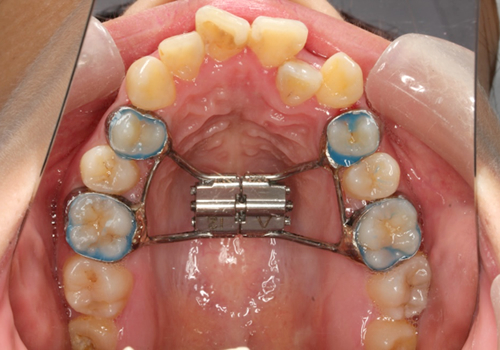

症例03. 急速拡大装置

上あごの幅を拡げるための装置です。正中口蓋縫合と呼ばれる骨の結び目に作用し、骨ごと拡大します。

| 治療内容 | 1:上あごが狭く、交差咬合になっている 2:朝夕2回スクリューを回してもらう 3:正中は離開し、幅が拡がったのがわかる |

|---|---|

| 期間 | 半年 |

| 費用 | 300,000円+税 |

| リスク | 拡げた際の痛みが数日出ることがあります。 |